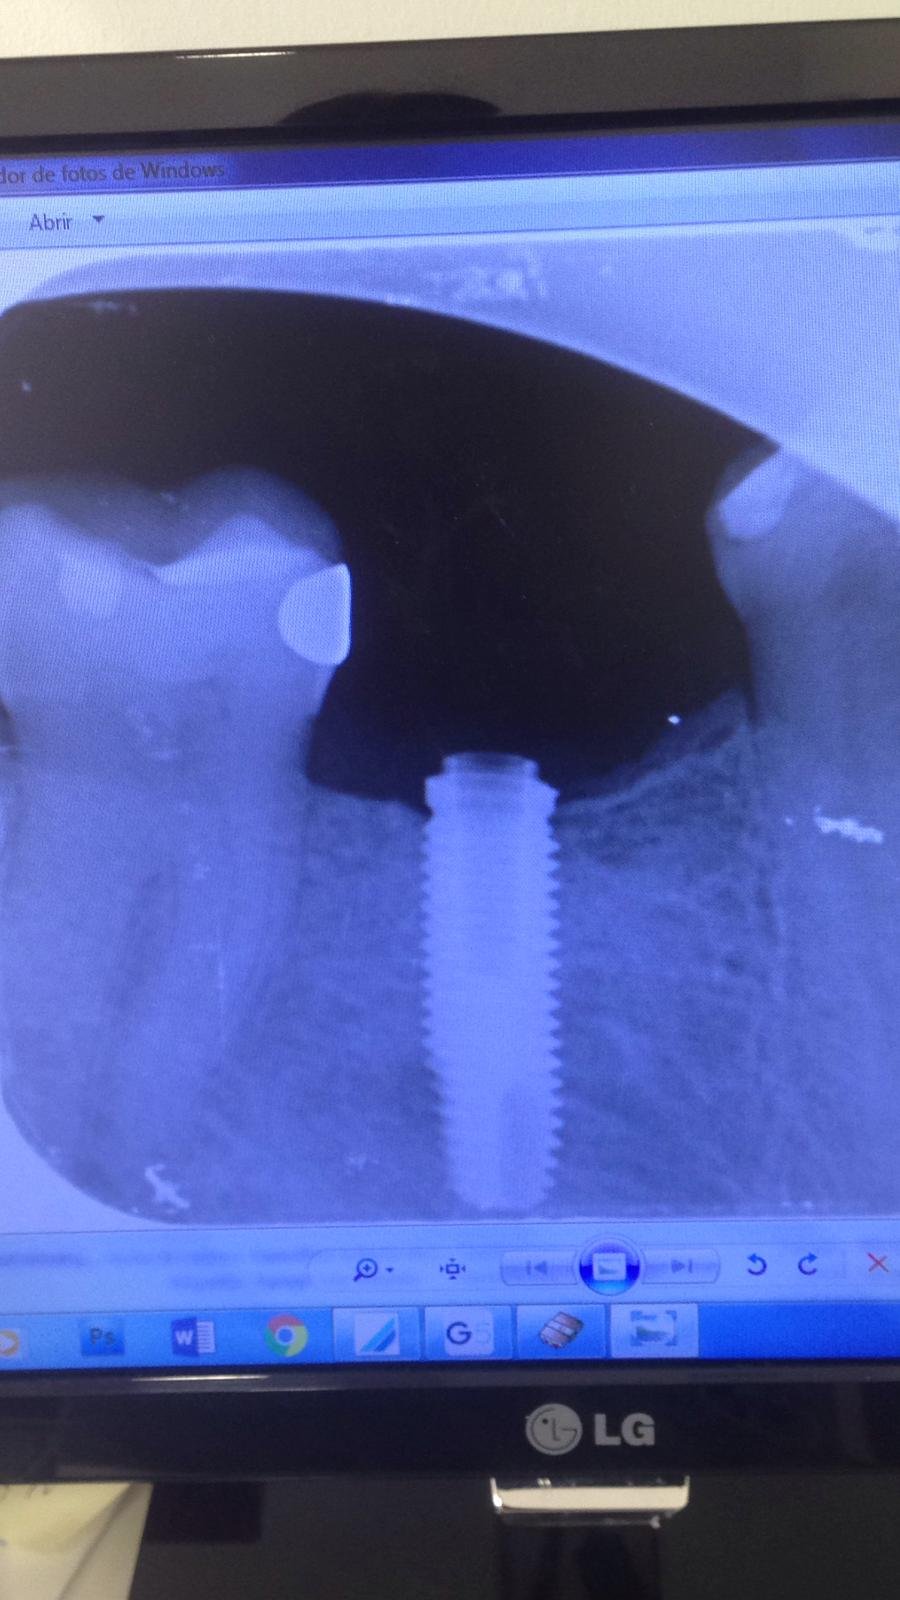

Implante en 46 que se le afloja el tornillo

Hola: Este paciente tiene un implante antiguo en el 46. Ultimamente se le aflojó, se lo apreté, y se le ha vuelto a aflojar un par de veces. El tornillo [...]